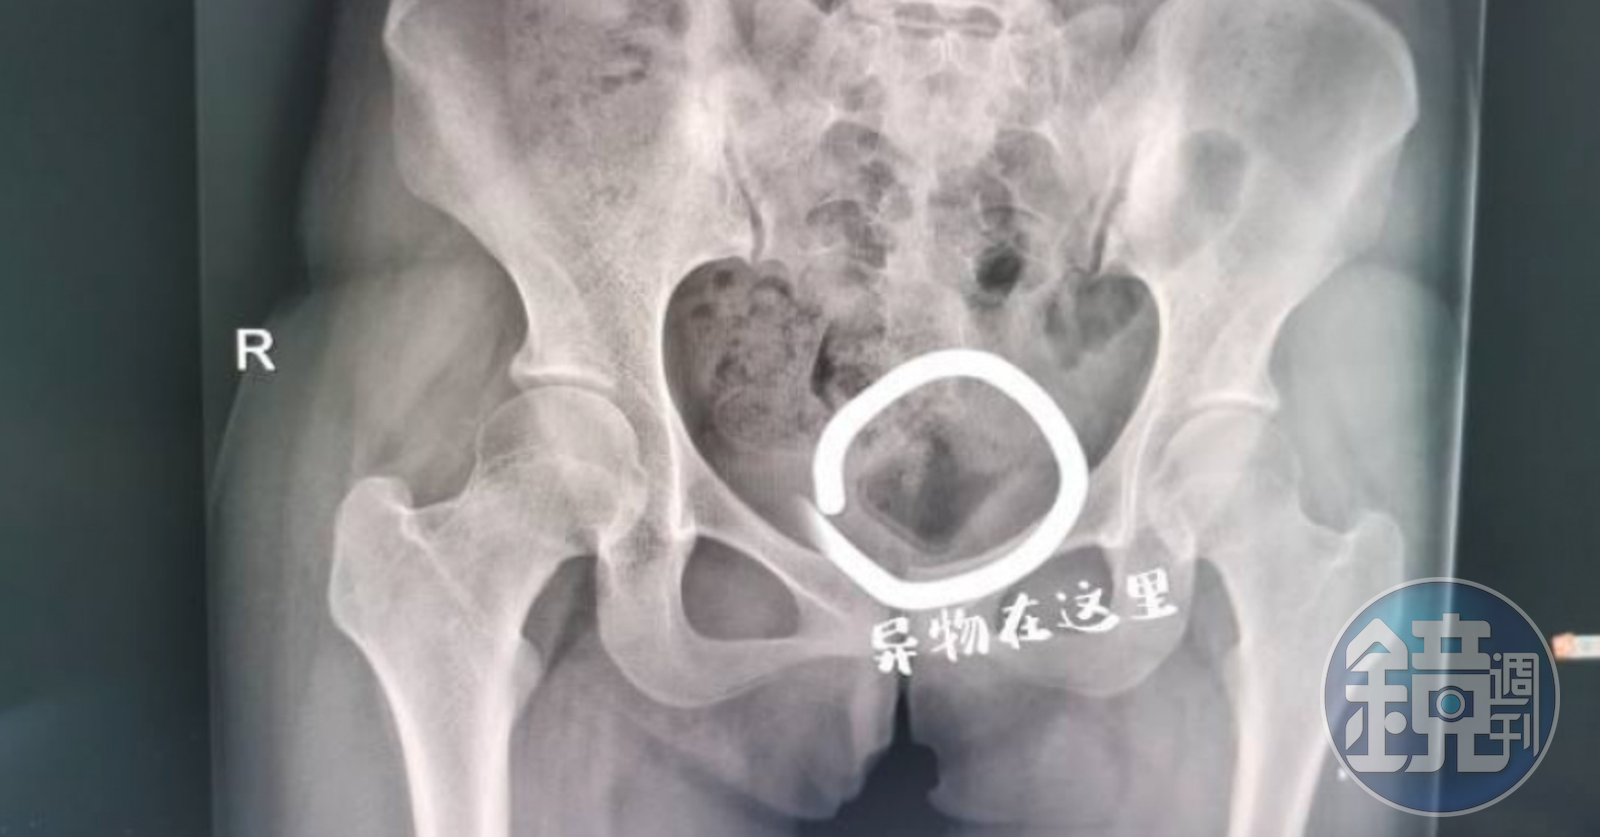

經檢查發現,瓶蓋表面光滑、無著力點,靠一般的醫療器材無法順利取出,所幸位置不算深,改用超音波引導,最終用手術鉗取出了小楊體內的異物,原來是個長5公分寬3公分、類似化妝品蓋子的東西。